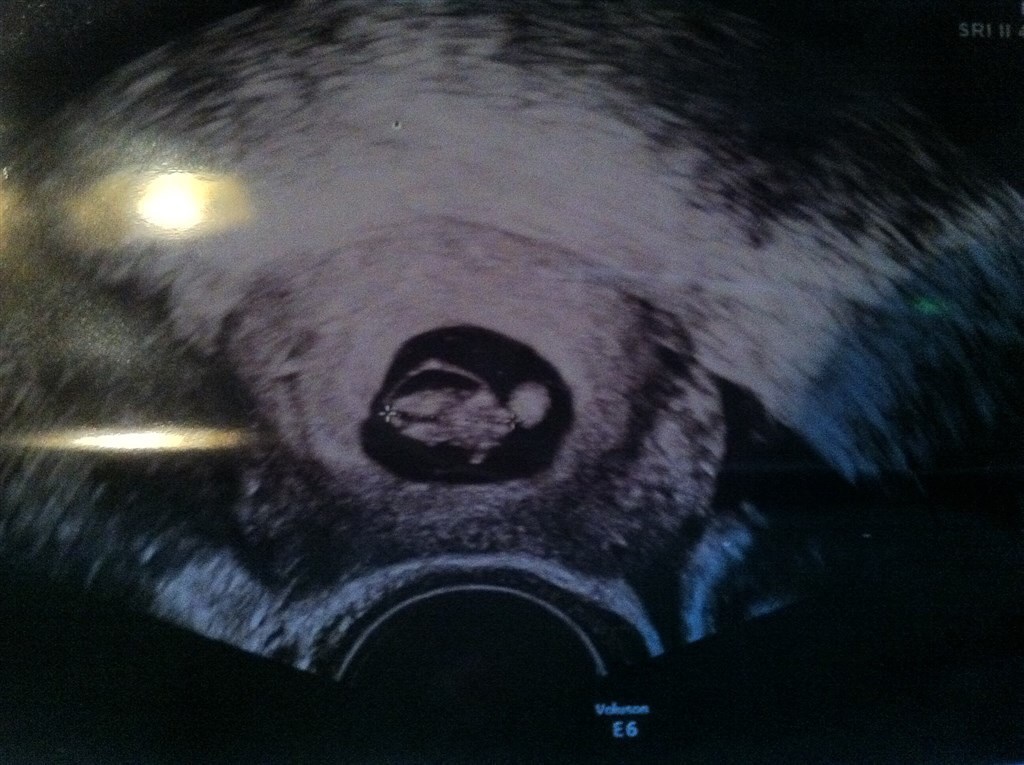

Her er jeg i uge 9+6

Vedhæftede fotos (klik for at se i fuld størrelse)

Anmeld